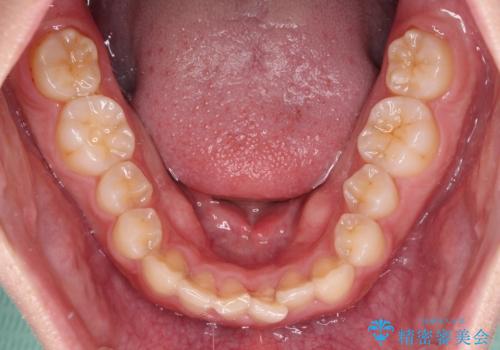

捻れて前に出ている前歯 ワイヤー装置での非抜歯矯正

- 捻れて前に出ている上顎前歯と全体的なデコボコを気にして来院された患者様です。

舌の突出癖がなかなか改善されず、上下前歯が接触するようになるまでに長期間を要しました。